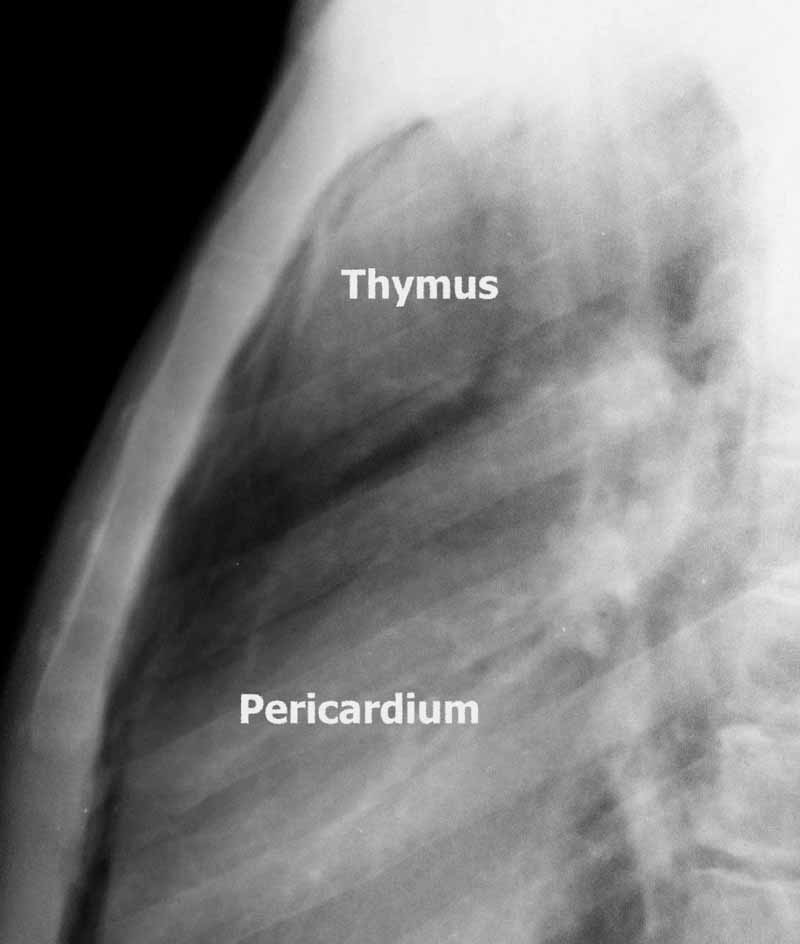

To facilitate the dissection and to shorten operative time, adjuvant pneumomediastinum is routinely performed 24 hours before the operation by introducing a Veress needle under local anesthesia at the level of the suprasternal notch, behind the posterior wall of the sternum [2]. Afterwards, 400 to 600 mL of air is insufflated in a sterile manner at a rate of 25 mL/min. Through this simple and safe maneuver, the thymus is progressively separated from the surrounding structures (Figure 1).

View image largerFigure 1. Chest x-ray showing a large thymus separated from the surrounding structures due to preoperative pneumomediastinum. View image largerFigure 2. Placement of the trocars.